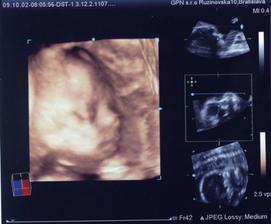

Naše krásne dievčatko